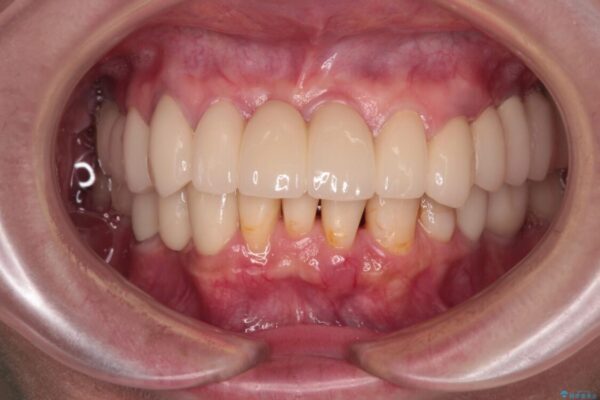

治療後

• 放置したインプラントとインビザライン 全顎リカバリー治療 治療後画像